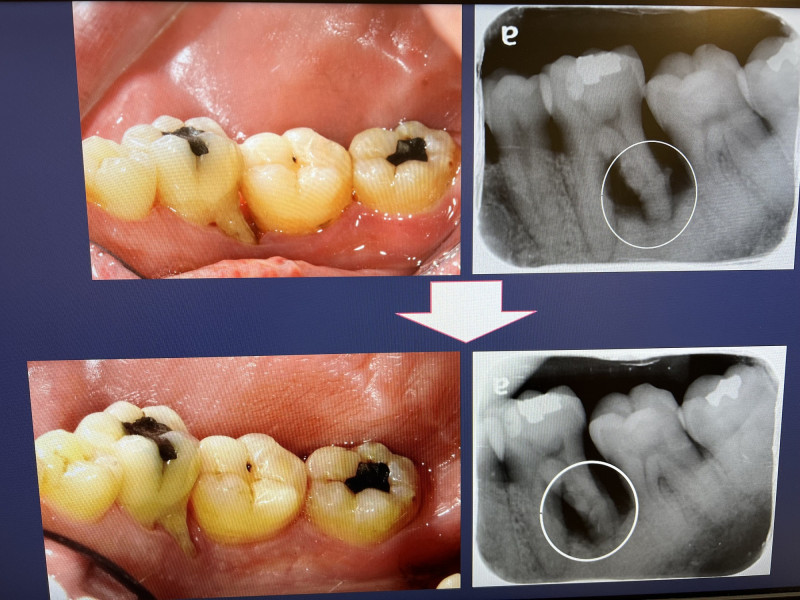

〔記者王俊忠/台南報導〕45歲徐先生過去長期潔牙不良,牙齦常出血、牙齒易敏感酸痛,到成大醫院求診,診斷是局部重度牙周炎,右下與左下大臼齒因嚴重齒槽骨破壞,預後不佳、建議拔掉左下大臼齒。患者希望儘可能保住牙,歷經1年積極非手術性治療,同時努力潔牙、規律回診,並以自費抗菌光動力療法輔助治療牙周嚴重受損區域。徐先生不僅保住牙齒,還改善牙齦出血與牙齒敏感症狀。

成大醫院牙周病科主治醫師丁羣展表示,台灣患者對於牙周病治療需求日益增加,據衛福部口腔健康司調查,台灣成年人牙周病盛行率高達8成,其中有一半處於嚴重狀況。重度牙周病的牙周囊袋深度通常較深,並伴隨齒槽骨嚴重破壞,因為預後不佳,不適合做牙周再生手術,牙醫師大多會建議拔掉牙齒,然而大部分患者仍希望保留自己牙齒。針對這類情況,只能進行保守性牙周治療,並加強口腔清潔,儘量減少口腔內的牙周致病菌。

丁羣展說,針對牙周破壞較嚴重的牙齒,除了使用抗生素等藥物治療外,光動力療法 (Photodynamic therapy, PDT) 最近成為新的治療選擇。針對細菌下手的光動力療法稱為抗菌光動力療法,此療法是利用光感劑將細菌染色,並使用適當波長和低輸出能量密度的雷射對牙齒患部照射,以達到牙周囊袋內殺菌的目的。抗菌光動力療法搭配非手術牙周性治療,顯著可改善且穩定牙周炎患者的臨床症狀。